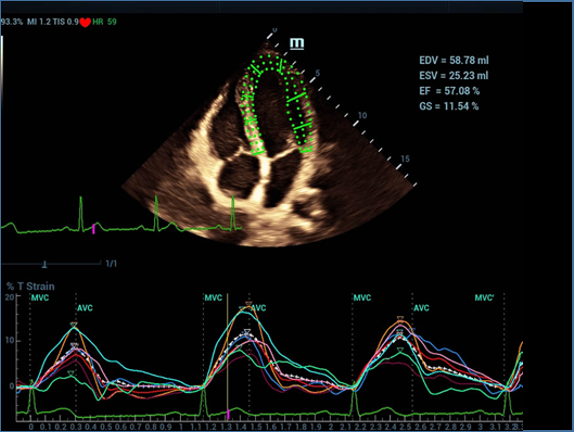

Resona 7, ĂŒstĂŒn dĂŒzeyde g?rĂŒntĂŒ kalitesine ek olarak, vaskĂŒler hemodinamik de?erlendirmesi i?in devrim niteli?indeki V Ak??? ile fetĂŒs CNS tan?lamas? i?in 3 boyutlu veri kĂŒmesinden dĂŒzlem g?rĂŒntĂŒsĂŒ alma konusunda en iyi birime sahip oldu?undan, klinik ara?t?rma yeterliklerini de art?rmaktad?r. En sezgisel, harekete dayal? ?oklu dokunmatik i?letim ile tĂŒm temel klinik ?zellikleri bir araya getiren Resona 7, ultrason yenili?i konusunda ger?ek anlamda yeni dalgalara ?ncĂŒlĂŒk ediyor.